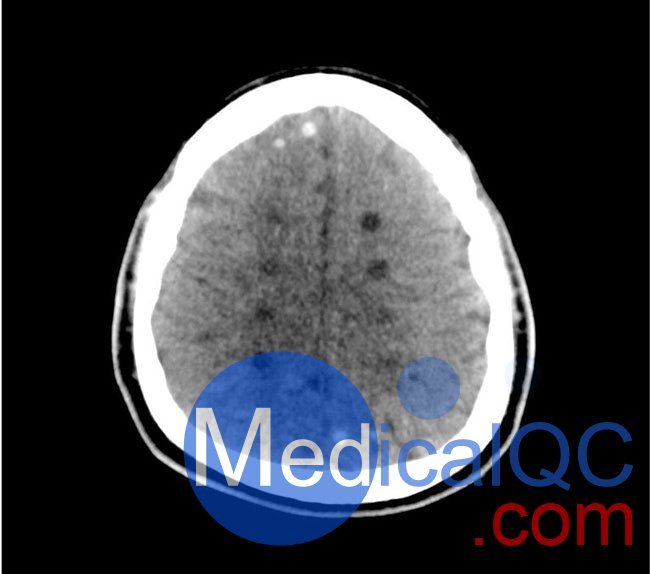

50-01頭部CT模體,50-01腦中風(fēng)頭部模體,50-01腦出血頭部模體模擬了具有中風(fēng)和出血模式的頭部。它覆蓋枕骨大孔的頂點(diǎn)。

卒中模式包括早期梗死的體征(大腦中動(dòng)脈高密度、基底神經(jīng)節(jié)消失)、急性和亞急性分水嶺梗死以及不同年齡的腔隙性梗死。

出血模式包括蛛網(wǎng)膜下腔出血、不同年齡的硬膜下出血、腦室內(nèi)出血和腦出血。

中風(fēng)

• 高密度大腦中動(dòng)脈 (MCA) 和左側(cè)基底神經(jīng)節(jié)消失

• 大腦中/后動(dòng)脈 (MCA/PCA) 和大腦前動(dòng)脈/中動(dòng)脈 (ACA/MCA) 領(lǐng)域的分水嶺梗死

• 8 個(gè)不同年齡的腔隙性梗死

出血

• 蛛網(wǎng)膜下腔出血(2個(gè)地區(qū))

• 不同年齡的硬膜下出血(3個(gè)地區(qū))

• 腦室內(nèi)出血(左側(cè)腦室)

• 腦出血(2 個(gè)丘腦,6 個(gè)皮質(zhì)下)

50-01頭部CT模體,50-01腦中風(fēng)頭部模體,50-01腦出血頭部模體影像效果圖: